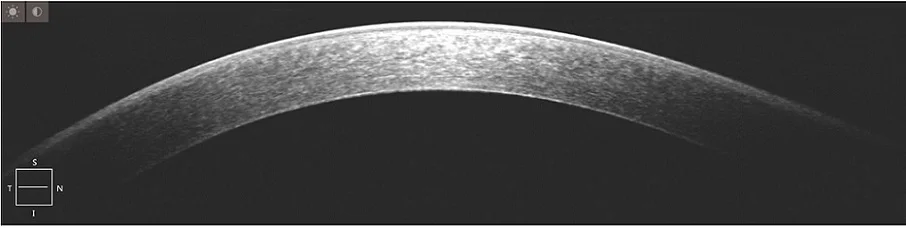

Measurement | Axial resolution(in tissue): 5μm(in tissue) |

Horizontal resolution(in tissue): 10μm(in tissue) | |

Scanning | Maximum a scanning speed: 20KHz, tolerance±5% |

Maximum scanning depth≥2.65mm(in tissue), tolerance±3% | |

Maximum scanning range: 12mm × 12mm, tolerance±5% | |

Light Source | Central wavelength: 843nm |

Light power≤740μm(at the Cornea) | |

Refractive compensation range: -20D~+20D | |